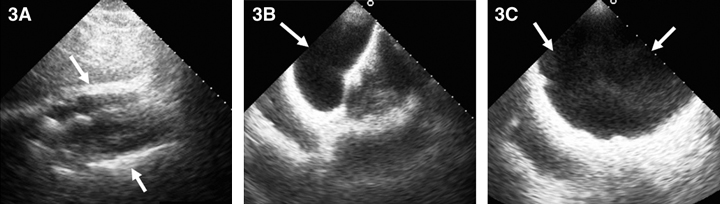

On the GHPS (Figure 1) a radiolucent pericardial halo was apparent, raising concerns for pericardial effusion. The rest of the study was unremarkable, with normal regional wall motion and quantitative ejection fraction of the cardiac ventricles. Comparison with a recent chest x-ray (Figure 2) revealed radiolucency external to the chest wall. Subsequent transthoracic echocardiography (Figure 3) ruled out the presence of pericardial effusion.

3: Two-dimensional echocardiogram. 3A: Subcostal views showing pericardial border anteriorly and posteriorly (arrows) without evidence of pericardial effusion. 3B: Subcostal view with the transducer directed anteriorly to image the saline-filled breast implant (arrow). 3C: Anterior chest wall imaging depicting the implant (arrows). |